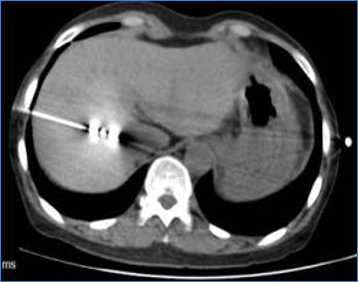

Liver Cancer

CT image of liver before treatment

Primary liver cancer, maximum diameter 4.3 cm

CT image of liver during MWA

CT-guided microwave ablation